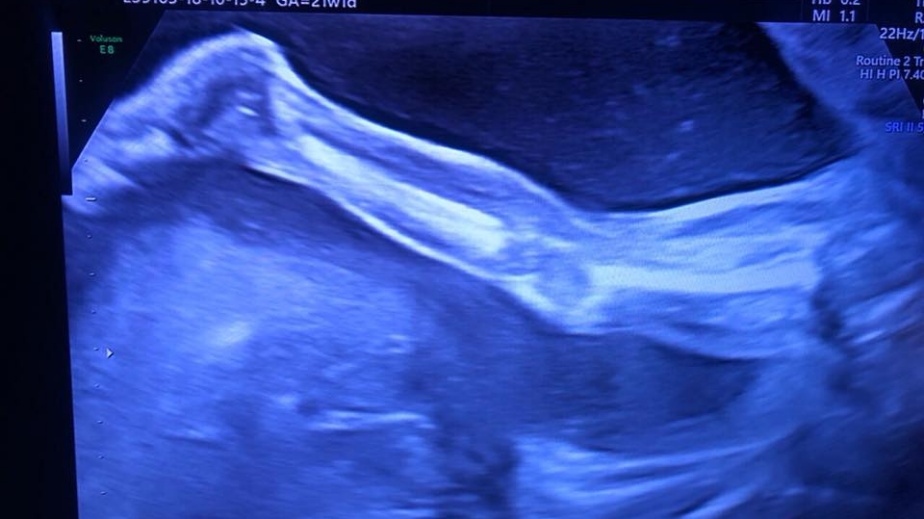

Бившият топ журналист, водещ и настоящ евродепутат Николай Бареков днес празнува своя 46-ти рожден ден. За радостната новина,че заедно със своята половинка Мария Календерска очакват своето трето дете се похвали самият той в личния си профил във фейсбук.

„Когато утре ставам само на 4+6, а подаръкът ще си го получа чак през 2019. Четвърти син, който може да стане и шампион по плуване като баща си. С тези огромни хубави крака няма голям избор.“, написа на стената си Бареков.

За него това е четвърти син, защото от брака си с първата си съпруга има голямо момче. За настоящата му половинка Мария това ще бъде трето дете.